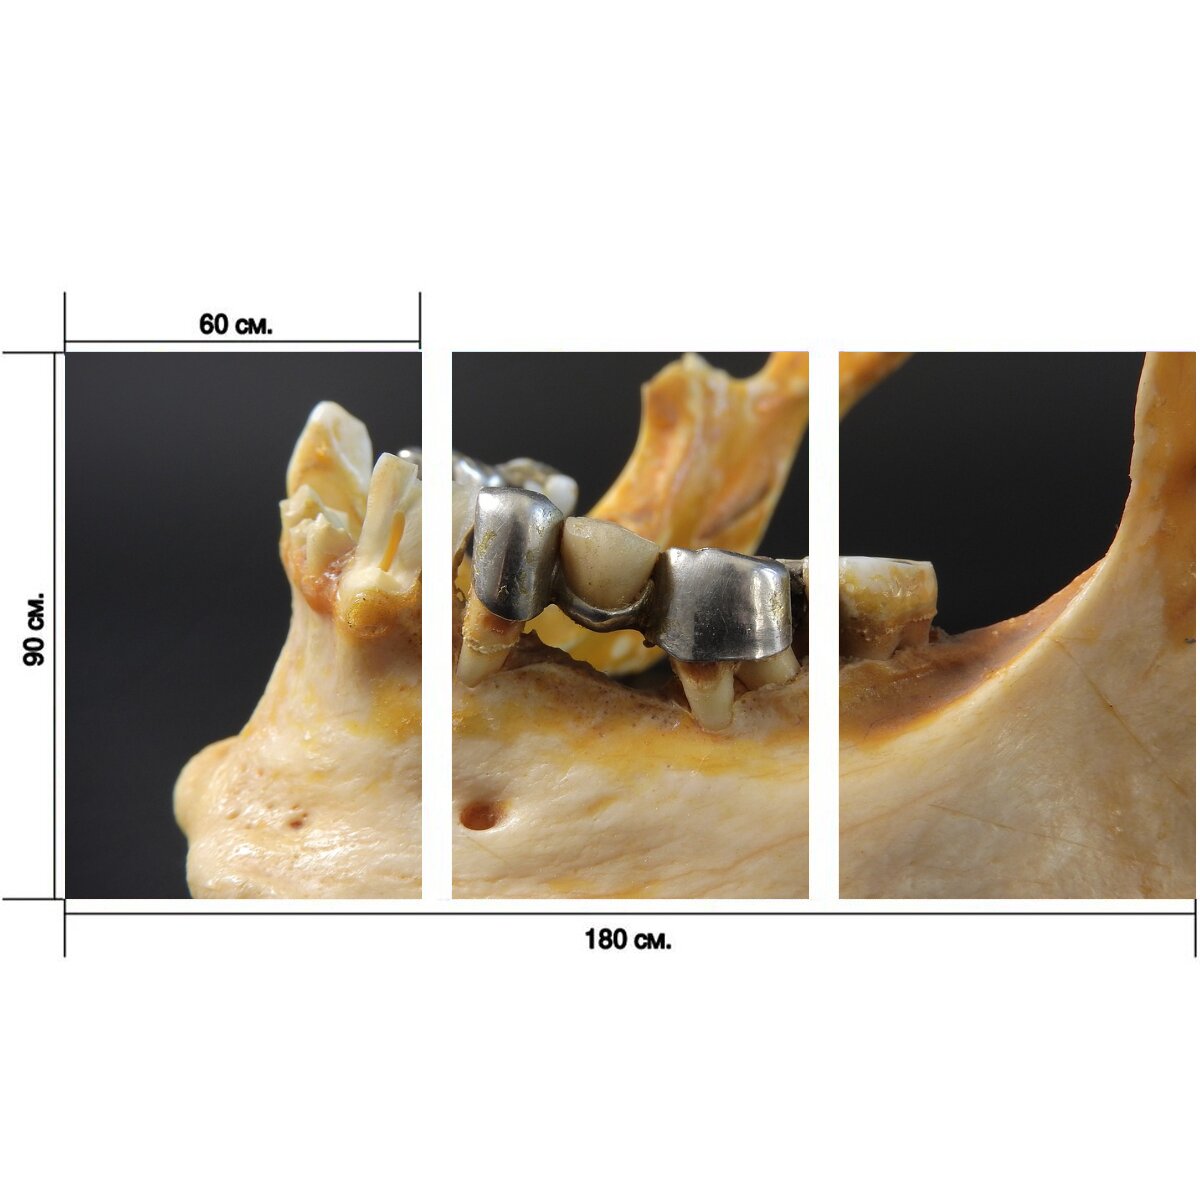

Большой Модульный постер - 180 х 90 см. 3 части - это идеальный выбор для тех, кто хочет украсить свой дом или офис ярким и стильным настенным декором. Постер состоит из трех отдельных модулей, которые можно размещать вместе или раздельно, создавая уникальные композиции и меняя общую атмосферу помещения.1